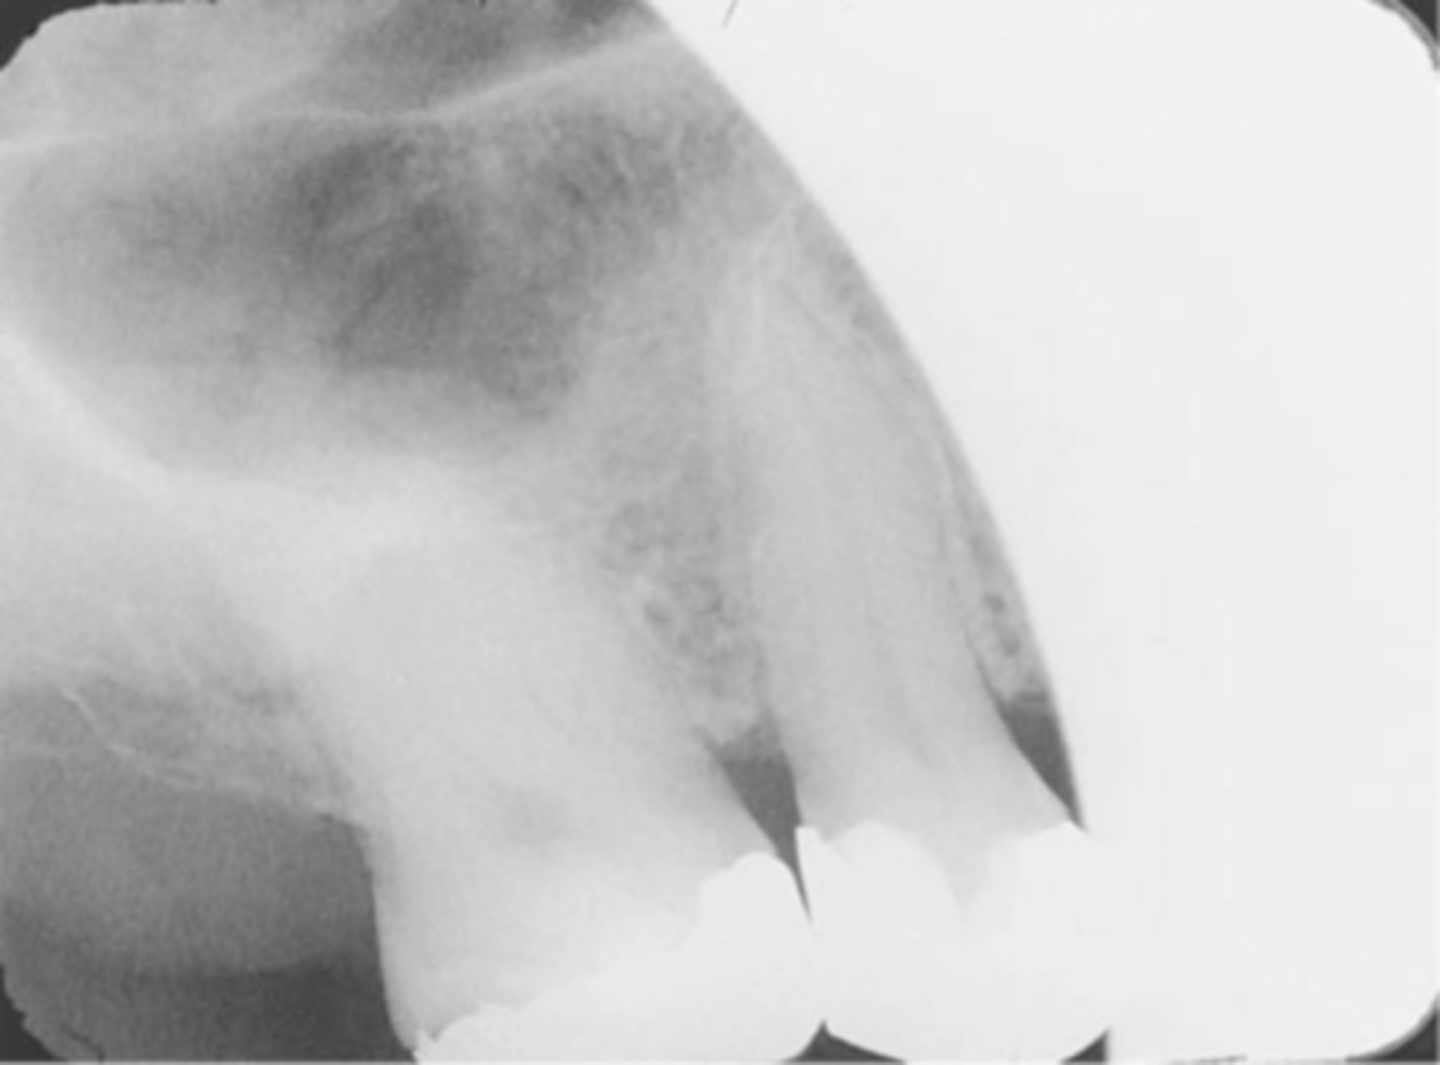

Incorrect Vertical Angulation-->Elongated Images

-Teeth appear long and distorted

-Vertical angulation was insufficient or too flat, resulting in images that are longer then the actual teeth.

-Occurs more often with the bisecting technique

-To prevent use adequate vertical angulation

Tube Head & PID-->Elongation of the Image

-Bisecting technique error

-Insufficient Angulation (not steep enough), causing elongation or increased anatomy of the teeth and cutting off apex.